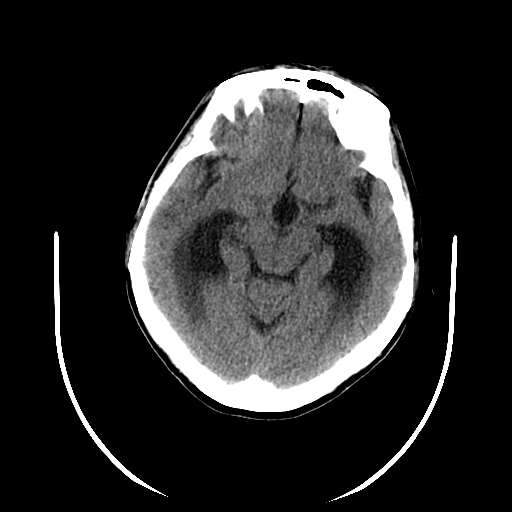

以下是引用hhcckk在2007-10-9 10:03:00的发言:[br]galen';s静脉瘤又称大脑大静脉瘤,是由于动静脉短路,大量血流进入galen';s静脉(大脑大静脉),造成该静脉瘤样扩张所致,病理上典型的galen';s静脉瘤包括一明显扩张的囊状galen';s静脉和引流galen';s静脉的短路血管,,这些短路血管多来源于颈内动脉系统或基底动脉系统,多异常扩大、迂曲。巨大的galen';s静脉瘤可造成中脑压迫,导水管闭塞,引起梗阻性脑积水。[br]galen';s静脉瘤ct表现较典型,根据其部位、形态、增强前后表现及脑积水表现较易诊断。[br]支持张主任,此病人病灶强化明显,正常松果体增强后在病灶的后方可见,可以再做个mr,血管性的病灶在mr上有流空效应,增强后明显强化,诊断更有把握